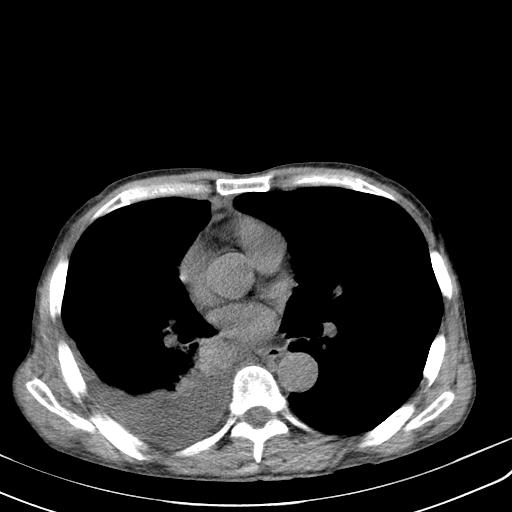

男性 75  咳嗽 一周前发热最高达39

右肺继发型tb并右侧tb性胸腔炎,右侧胸腔大量积液并右下肺膨胀不全,慢支肺气肿、多发肺大泡。建议抽胸水实验室检查并复查排除恶性在占位。

右上肺继发型肺结核,右胸腔中等量积液。

左上肺大泡。

结核的基础上有纵隔淋巴结肿大,右侧有胸水,但右侧纵隔反而窄,说明有肺有不张。

再就是右下肺有块影,和不张混合,还是不能除外肺癌。

1)右肺继发型肺结核。2)左肺胸膜下多发性肺大泡。3)右侧胸腔积液。